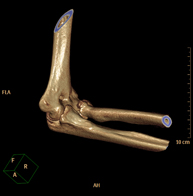

Exploración radiológica que mediante un sistema de rayos X y detectores que giran alrededor del paciente, reconstruyendo las imágenes por ordenador (TC Multidetector), permite el estudio de huesos, músculos y articulaciones del hombro. - TC Codo

Exploración radiológica que mediante un sistema de rayos X y detectores que giran alrededor del paciente, reconstruyendo las imágenes por ordenador (TC Multidetector), permite el estudio de huesos, músculos y articulaciones del codo. - TC Mano – muñeca

Exploración radiológica que mediante un sistema de rayos X y detectores que giran alrededor del paciente, reconstruyendo las imágenes por ordenador (TC Multidetector), permite el estudio de huesos, músculos y articulaciones de mano y muñeca. - TC Pelvis ósea